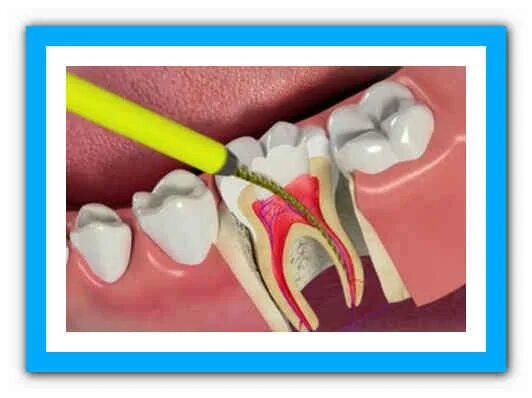

Пломбирование перфорации